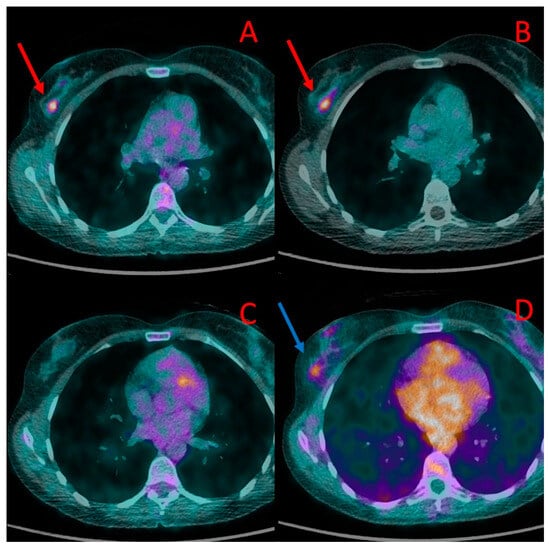

Figure 3. One of the brain metastases in patient #4 detected in [18F]PSMA-1007 (B) but not in [18F]FDG PET/CT (A). Diffuse liver metastases showed higher uptake of [18F]PSMA-1007 (D) than of [18F]FDG (C). More bone metastases in the left femoral bone were detected, and higher radiotracer accumulation in these lesions was found in 18F-PSMA PET/CT (F) in comparison to [18F]FDG (E).

Altogether, bone metastases were found in five patients (#4, 5, 8, 9, and 10). PET-positive bone lesions characteristic of bone metastases were found in both PET/CT modalities in three patients (#4, 5, and 8). In all of them, the SUVmax values measured in the bone lesions were higher in PET/CT with [18F]PSMA-1007 (6.8, 9.8, 18.1) than with [18F]FDG (3.8, 5.3, 16.7, respectively), with TBR in [18F]PSMA-1007 5.7, 8.2, 15.0 and in [18F]FDG 3.2, 7.6, 11.9, respectively (Figure 2 and Figure 3E,F). The number of bone metastases ranged from one lesion visible in both methods (#5) to uncountable lesions in two remaining patients (#4, 8), However, the number of [18F]PSMA-1007-positive lesions was higher than [18F]FDG -positive metastases in patient #8 (in particular, higher detectability of [18F]PSMA-1007 PET/CT was observed in cranial bones).

Liver metastases (up to 67 mm) showed higher [18F]PSMA-1007 uptake than [18F]FDG (SUVmax = 17.3 vs. 4.1, TBR 3.4 vs. 1.8) (Figure 3C,D).

Metastases in both adrenals (20 and 55 mm) also presented with higher [18F]PSMA-1007 accumulation than 18F-FDG (SUVmax = 11.7 vs. 2.3, TBR 2, 3 vs. 1.7).

Approximately ten small brain metastases (diameter ranging from 4 to 7 mm) were detected only with the use of [18F]PSMA-1007 PET/CT (they were [18F]FDG-negative) (Figure 3A,B). The central nervous system metastases were subsequently confirmed using brain MR.